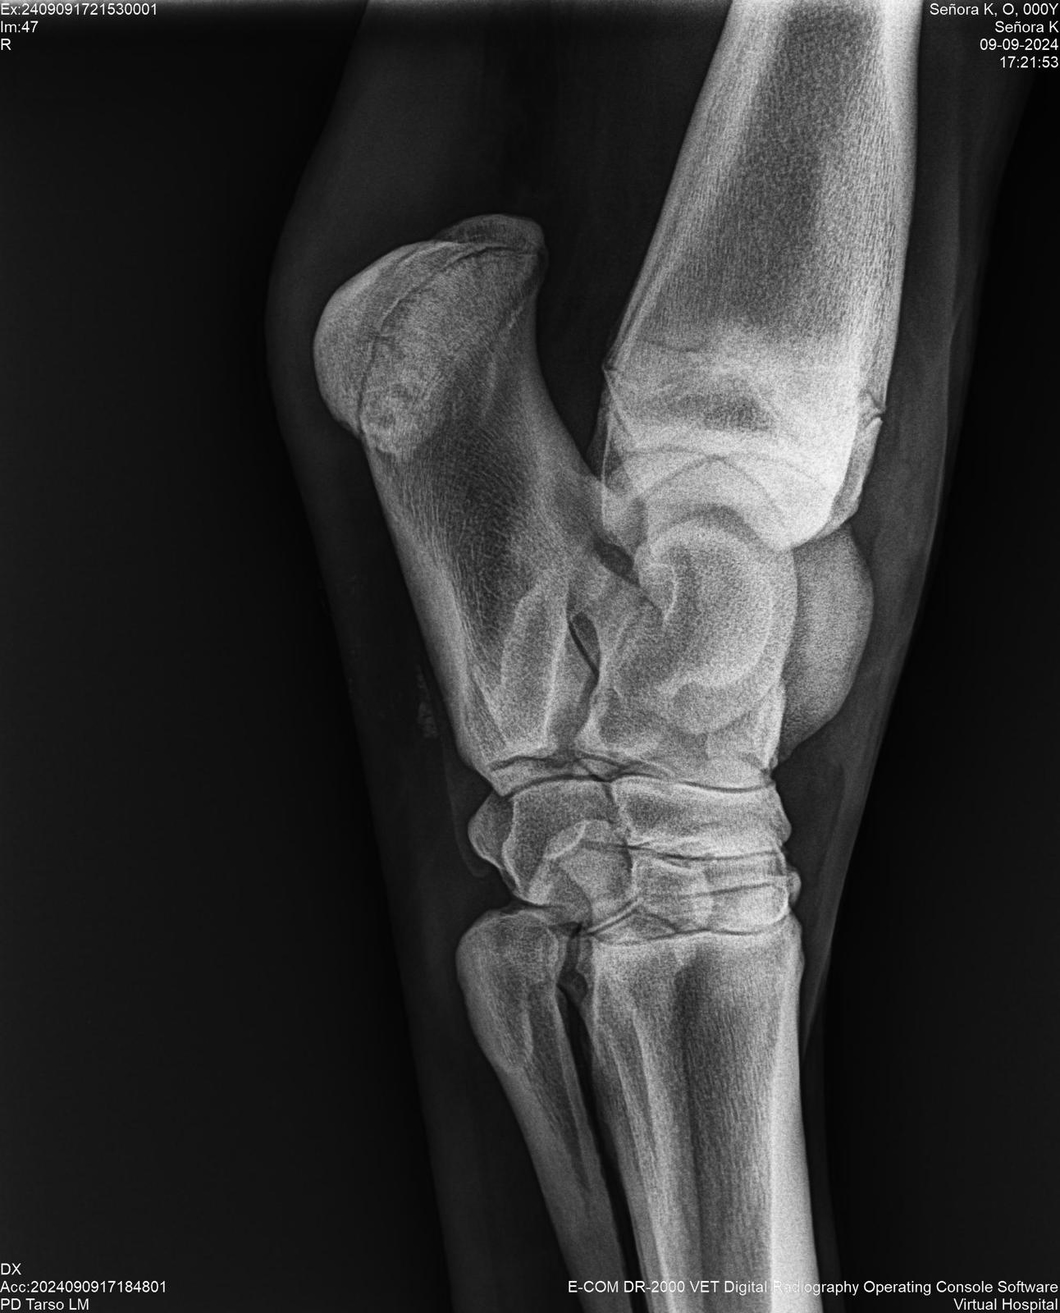

LOTE 44, SEÑORA K

Identificador: #291147-

Generacion 2022